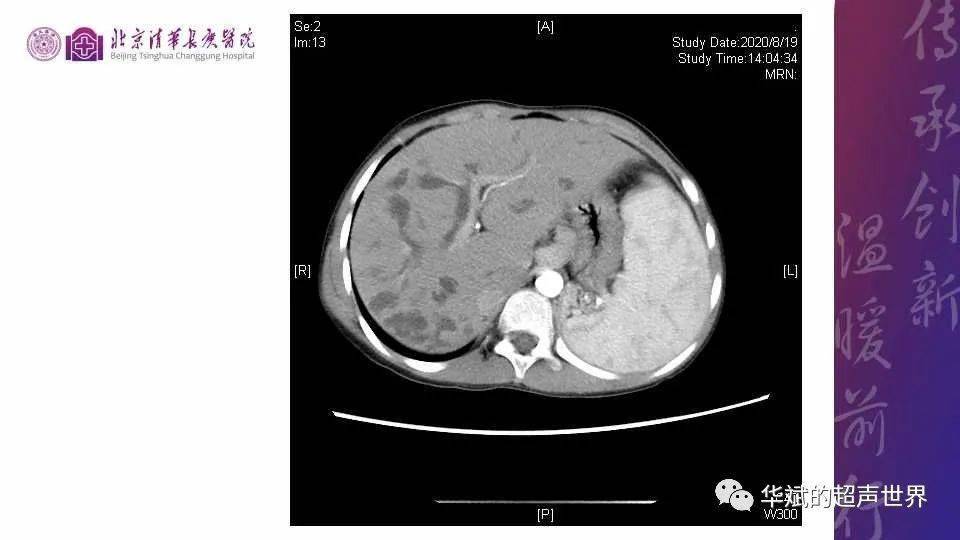

第12期住培小读片腹部caroli病

图片尺寸1080x608